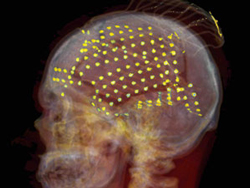

Pentru a se putea observa ce zone din creier sunt activate de cuvinte, voluntarii, precum și autorul principal al studiului, Alex Huth, au ascultat poveşti de la un program de radio american mai mult de două ore, în timp ce au stat nemişcaţi într-un scanner de rezonanţă magnetică nucleară.

Echipa a colectat date asupra modificărilor fluxului sanguin şi a oxigenării sângelui – indicatori de activitate – în diferite arii ale cortexului cerebral (stratul cel mai exterior al ţesutului cerebral, jucând un rol cheie în funcţii mai înalte, cum sunt limbajul şi conştienţa). Datele imagistice ale creierului au fost comparate cu transcrierile în funcţie de ora, minutul, secunda din poveştile ascultate. Cercetătorii au utilizat apoi un algoritm pe computer care dădea un scor cuvintelor în funcţie de cât de apropiate erau ca semnificaţie.

Rezultatele au fost convertite într-o hartă de tip thesaurus, unde cuvintele au fost aranjate pe emisferele stângă şi dreaptă ale creierului. S-a observat că sistemul semantic este distribuit în peste 100 de arii distincte pe ambele emisfere ale cortexului şi în tipare complexe, care erau similare la persoanele care au participat la studiu.